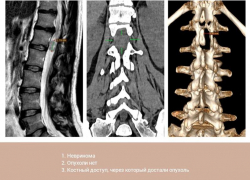

Опухоль из позвоночника через крошечный разрез удалили пациентке нейрохирурги Пятигорска

Почти год мучилась 28-летняя жительница Ставрополья от боли. Сначала у нее ныло в тазобедренном суставе, потом нога начала неметь, а затем появились проблемы...